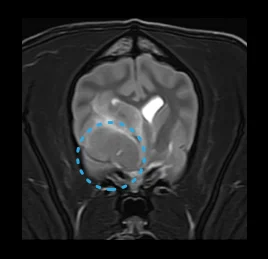

• 후두골 이형성 증후군